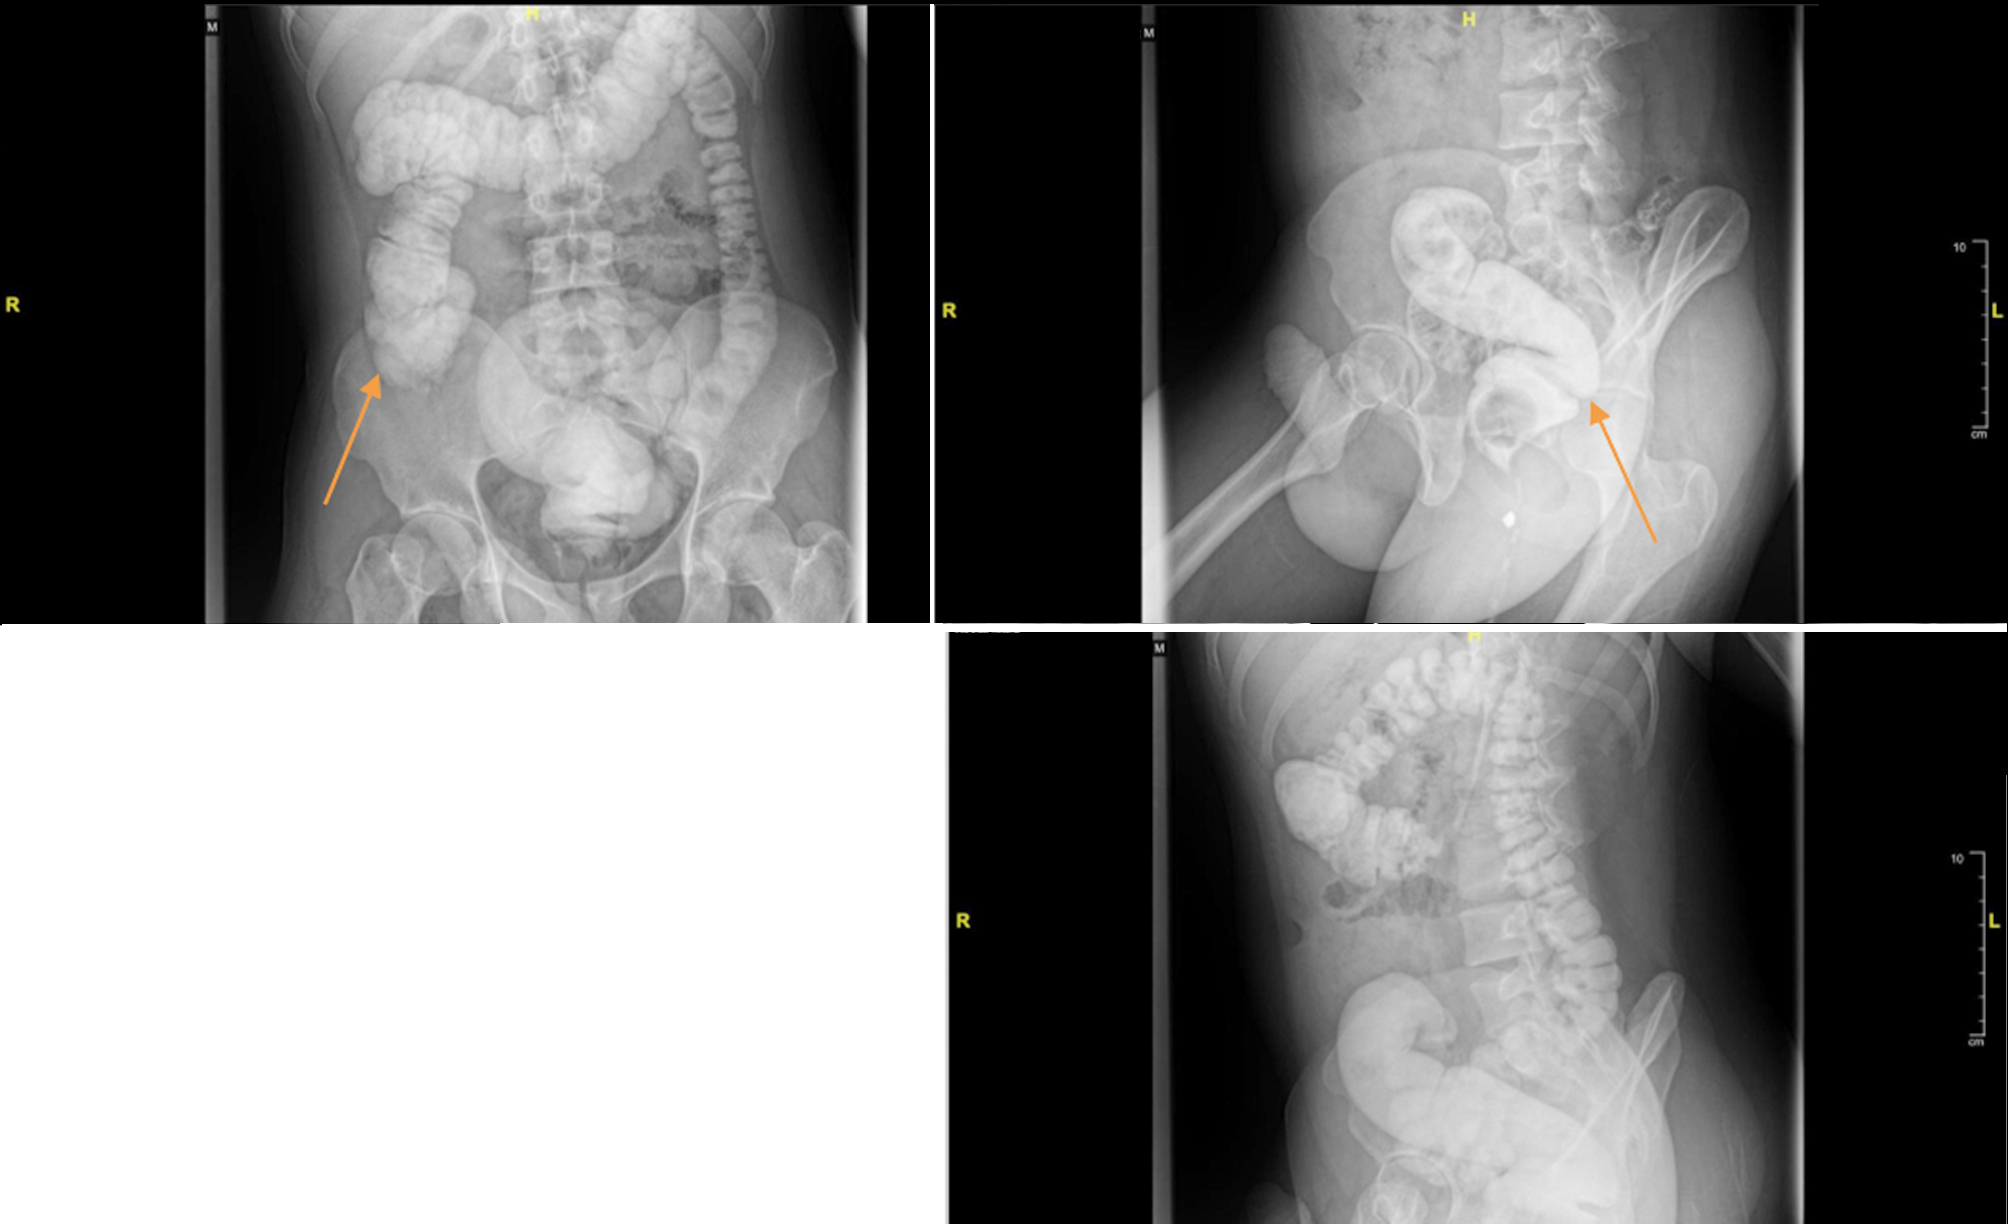

The patient had no difficulty with flatus, and there was no disturbance in urination. Vital signs were within normal limits. Physical abdominal examinations revealed distension but no pain upon palpation, and bowel sounds during auscultation were normal. We consulted the Physical Medicine and Rehabilitation Division to assess the potential for pelvic floor dysfunction, and the results were negative. A barium enema examination was performed to rule out Hirschsprung’s disease. Evaluation of colon structure abnormalities through the barium enema revealed a redundant ascending colon, hepatic flexure, and sigmoid, with no dilatation or filling defects in the colon (fig. 2). A biopsy was also performed, resulting in no aganglionic tissue.

Figure 2 - Barium enema pre-operative (July 2024): redundant ascendence colon, hepatic flexure, and sigmoid with no dilatation of colon

A barium enema evaluation was performed two months post-operative. The results showed no significant stenosis or filling defect in the visualized colon, with no visible redundancy of the sigmoid (fig. 3).

Figure 3 - Barium enema post-operative (September 2024): no stenosis and filling defect on the visualized colon with no visible redundancy of the sigmoid compared to pre-operative (shown with the orange arrow).